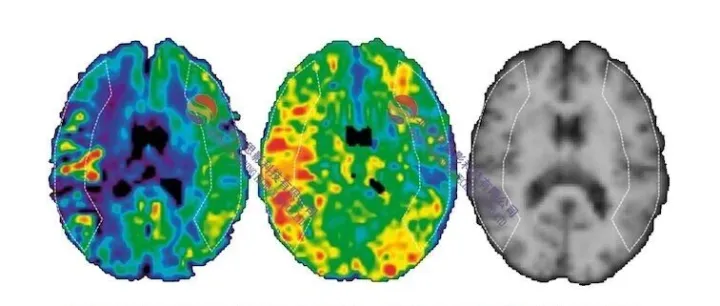

第二十二届磁共振ASL(动脉自旋标记)数据处理班(北京,12.4-7)

思影科技将于2025年12月4日-7日在北京举办第二十二届磁共振ASL(动脉自旋标记)数据处理班:基于SPM的ASL数据处理;脑影像多指标耦合分析;ASL扫描参数,BASIL分析与ATT计算;Expl